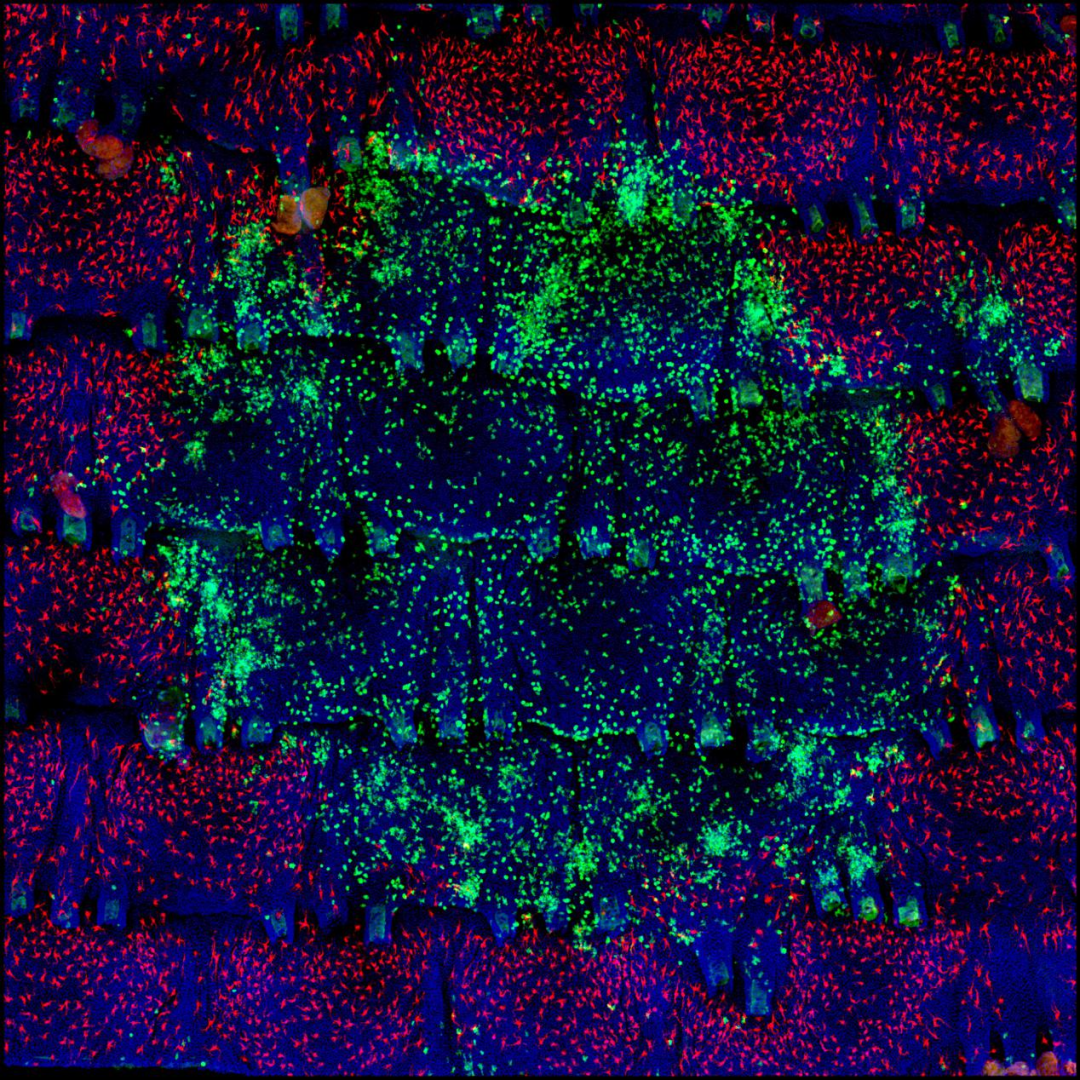

白癜风原创突破背后:一部历时六年的“失败简史”

图6 白癜风进展微观图,绿色的为CD8+T细胞,红色的为黑色素细胞 | 徐子健供图

“那到底是谁,通过什么方法招募CD8+T细胞呢?” 徐子健问。